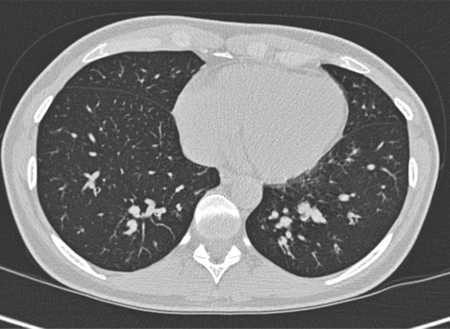

Bronquiectasia

Sinais do anel de sinete em uma mulher de 20 anos de idade com bronquiectasia

De Pamela J. McShane, MD; uso autorizado